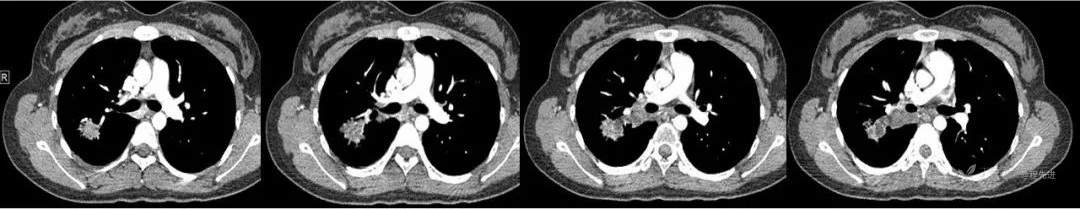

又3个月后,患者停药后复查,右上肺结节较前明显增大。现为进一步诊治,遂于今日来我院就诊。

1年后术前复查